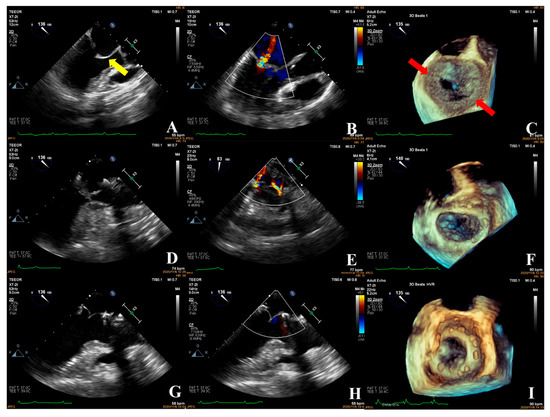

Current Usefulness of Transesophageal Echocardiography in Patients Undergoing Transcatheter Aortic Valve Replacement

This review article describes in depth the current usefulness of transesophageal echocardiography in patients who undergo transcatheter aortic valve replacement. Pre-intervention, 3D-transesophageal echocardiography allows us to accurately evaluate the aortic valve morphology and to measure the valve annulus, helping us to choose the [...] Read more.

This review article describes in depth the current usefulness of transesophageal echocardiography in patients who undergo transcatheter aortic valve replacement. Pre-intervention, 3D-transesophageal echocardiography allows us to accurately evaluate the aortic valve morphology and to measure the valve annulus, helping us to choose the appropriate size of the prosthesis, especially useful in cases where the computed tomography is not of adequate quality. Although it is not currently used routinely during the intervention, it remains essential in those cases of greater complexity, such as for patients with greater calcification and bicuspid valve, mechanical mitral prosthesis, and “valve in valve” procedures. Three-dimensional transesophageal echocardiography is the best technique to detect and quantify paravalvular regurgitation, a fundamental aspect to decide whether immediate valve postdilation is needed. It also allows to detect early any immediate complications such as cardiac tamponade, aortic hematoma or dissection, migration of the prosthesis, malfunction of the prosthetic leaflets, or the appearance of segmental contractility disorders due to compromise of the coronary arteries ostium. Transesophageal echocardiography is also very useful in follow-up, to check the proper functioning of the prosthesis and to rule out complications such as thrombosis of the leaflets, endocarditis, or prosthetic degeneration. Full article